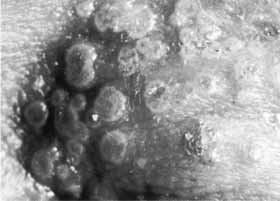

The follicular conjunctivitis of primary herpes is associated with a regional adenitis. Typically, the ipsilateral preauricular lymph node is slightly enlarged and a little tender. Swollen lids and a primary skin lesion are often readily apparent (Figs. 3 and 4), but on occasion only a careful search will reveal the single or grouped vesicles of crusted ulcers (Figs. 5 and 6) hidden among the lashes or in the intermarginal strip. Similar lesions may be located elsewhere on the face or at the mucocutaneous junction of the mouth, in the nose, or on the trunk, and they may be easily missed unless a specific search is made. In nearly one fourth of cases, no cutaneous lesions are present.35 The conjunctiva is injected and edematous. Follicles develop, especially in the fornices, and extend to the tarsal areas (Fig. 7);they rarely occur at the limbus. Small subconjunctival ecchymoses are not uncommon and phylectenule-like lesions may develop on the globe (Fig. 8).

Fig. 6 Umbilicated primary herpetic lesions at the inner canthal area. (Courtesy of Dr. S. Darougar)

Fig. 7 Acute follicular conjunctivitis in primary herpetic infection: A Upper tarsus, B Upper fornix, C Lower fornix. (Courtesy of Dr. S. Darougar)